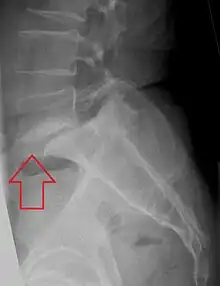

| X-ray of the lateral lumbar spine with a grade III anterolisthesis at the L5-S1 level | |

Spondylolisthesis is the displacement of one spinal vertebra compared to another. While some medical dictionaries define spondylolisthesis specifically as the forward or anterior displacement of a vertebra over the vertebra inferior to it (or the sacrum),[1][2] it is often defined in medical textbooks as displacement in any direction.[3][4] Spondylolisthesis is graded based upon the degree of slippage of one vertebral body relative to the subsequent adjacent vertebral body.[5] Spondylolisthesis is classified as one of the six major etiologies: degenerative, traumatic, dysplastic, isthmic, pathologic, or post-surgical.[6] Spondylolisthesis most commonly occurs in the lumbar spine, primarily at the L5-S1 level, with the L5 vertebral body anteriorly translating over the S1 vertebral body.[6]

Classification by degree of the slippage, as measured as percentage of the width of the vertebral body:[14] Grade I spondylolisthesis accounts for approximately 75% of all cases.[6]

- Grade I: 0–25%

- Grade II: 25–50%

- Grade III: 50–75%

- Grade IV: 75–100%

- Grade V: greater than 100%